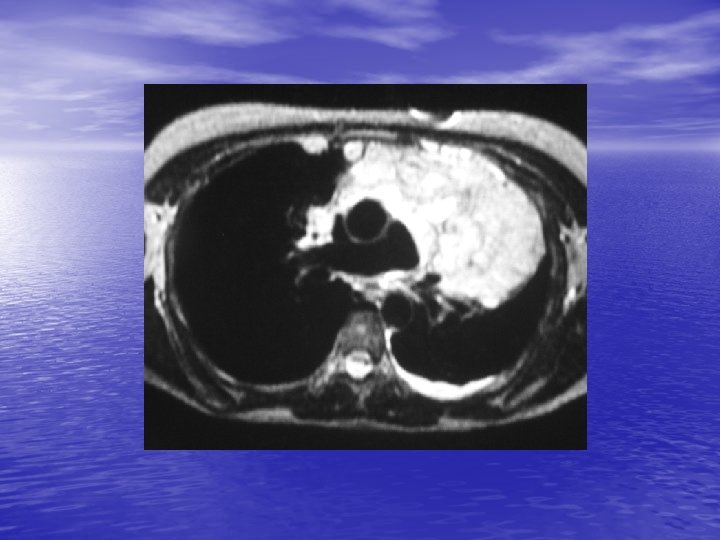

2. 3. IRM - Performances voisines de celle de la TDM pour le diagnostic positif et étiologique ; méconnaissance des calcifications. - Avantage pour le bilan préthérapeutique (mais TDM volumique). - Angio-MR pour le bilan des masses d’origine vasculaire.

5. MASSE DU MEDIASTIN POSTERIEUR 5. 1. Tumeurs neurogènes - Tumeur des nerfs périphériques (schwannome, neurofibrome), des ganglions sympathiques (ganglioneurome, neuroblastome), paraganglionnaires (chémodectome). - ++ gouttières costo-vertébrales, parfois calcifications, lésions osseuses associées évocatrices (trou de conjugaison élargi). - Rôle ++ de l’I. R. M. pour le bilan (recherche de prolongement intra-rachidien).